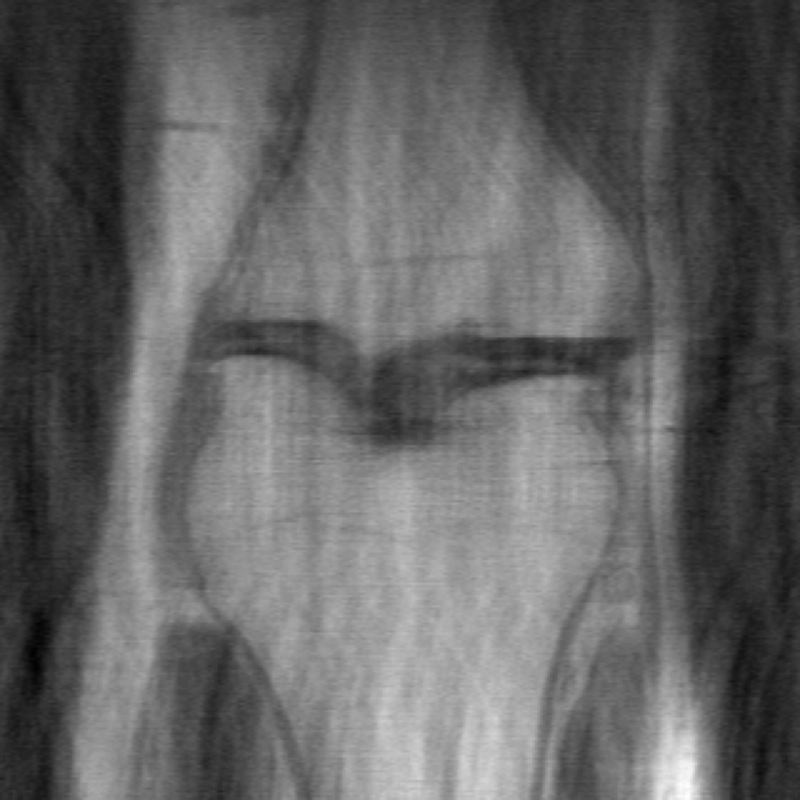

The data used in the undersampled MRI experiments were obtained from the NYU fastMRI Initiative [45]. The primary goal of the fastMRI dataset is to test whether machine learning can aid in the reconstruction of medical images. We trained and tested on a subset of the single-coil knee dataset, which consist of simulated single-coil measurements. In all tests, we use complex-valued data, which interfaces with our deep networks by treating the real and imaginary parts of the images as separate channels. We measure reconstruction accuracy with respect to the center 320320 pixels of the complex IFFT of the fully-sampled k-space data. For the purpose of visualization, we display only the magnitude images in the following sections.

In Table 1 we present our main results. We present sample reconstructions for the deblurring problem and MRI reconstruction problem in Figs. 7 and 8. For reference, the ground truth, inputs to the networks, a total variation regularized reconstruction, and a RED reconstruction are presented in Figs. 5 and 6. We also provide in the Appendix a table of SSIM values as well as the full version of Table 1, which contains the standard deviations of PSNR.

While the magnitude of the improvements vary across domains and problems, we find that retraining the network with the proposed model adaptation techniques significantly improve performance by several dBs in the new setting. This effect is particularly striking in the case of MRI reconstruction with MoDL, where the βnaiveβ approach of replacing with in the network gives catastrophic results (a roughly 9 dB drop in reconstruction PSNR), while the proposed model adaptation approaches give reconstruction PSNRs within 1-2 dB of the baseline approach of training and testing with the same forward model in the case where is known.